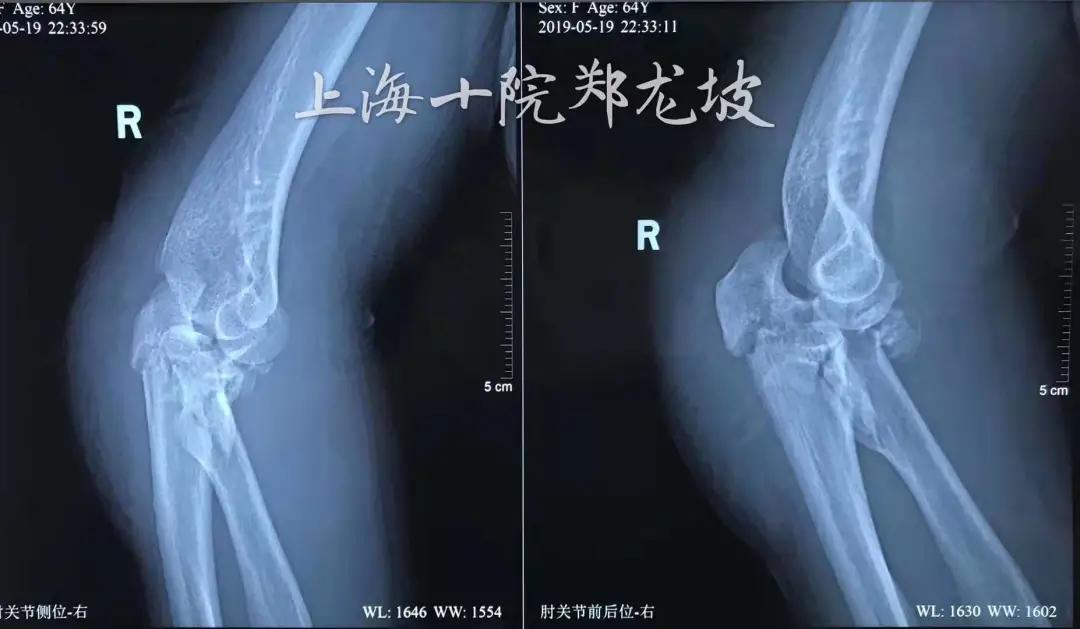

患者张阿姨64岁,不长前外出时,遇车祸导致右肘关节疼痛、活动受限,被送往上海十院救治,影像学检查提示肘关节恐怖三联征,合并尺骨鹰嘴骨折。

创伤骨科郑龙坡主任与团队充分讨论

指出患者为“向后孟氏骨折脱位”,

既尺骨鹰嘴骨折后脱位型,

合并有冠状突和桡骨小头的粉碎骨折,

比肘关节恐怖三联征治疗起来更有难度。